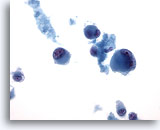

画像 1: 肝FNA – 良性肝細胞 良性肝細胞の小さな集塊。細胞は多角形のものもあれば円形のものもみられ、細胞境界は明瞭です。 核は中心性に位置し、周辺の細胞質は顆粒状を呈しています。細胞質内に色素沈着がみられます。小型の核小体がみられるものの、異型性および高N/C比は認められません。

60倍

画像 1

肝FNA – 良性肝細胞

良性肝細胞の小さな集塊。細胞は多角形のものもあれば円形のものもみられ、細胞境界は明瞭です。 核は中心性に位置し、周辺の細胞質は顆粒状を呈しています。細胞質内に色素沈着がみられます。小型の核小体がみられるものの、異型性および高N/C比は認められません。

60倍